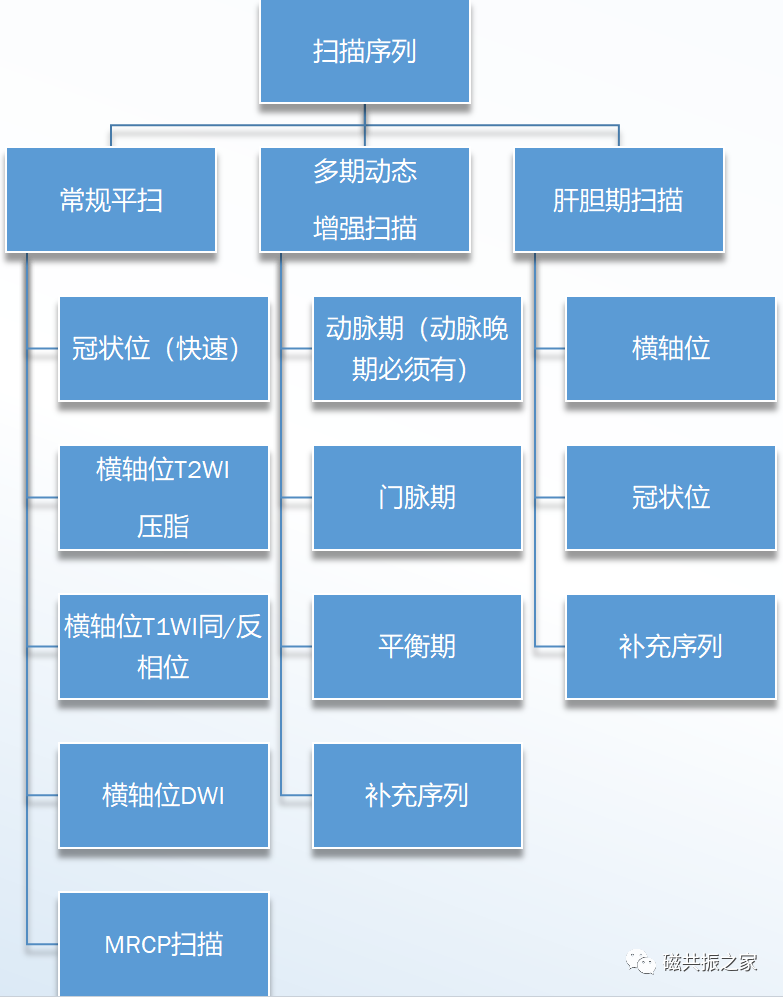

常规扫描序列:

| 平扫 | |

| 冠状面T2WI序列或稳态自由进动序列 | 屏气,建议1.5稳态,3.0 单次激发T2WI |

| 横轴面T1WI压脂序列 | 屏气,建议采用快速序列 |

| 横轴面同/相位序列 | 屏气,建议一出四序列 |

| 横轴面T2WI压脂序列 | 建议呼吸触发 |

| 横轴面DWI序列 | 建议呼吸触发 |

| 增强对比剂常规剂量0.1mmol/kg ,速率:2-3ml/s | |

| 横轴面多期动态增强序列 | 至少(蒙片-动脉晚期-门脉期-平衡期) |

| 冠状面增强补充序列 | 冠状面大范围更有利病变的评估 |

| 肝胆期增强序列(横+冠) | 使用肝胆特异性对比剂的需加扫肝胆期 |